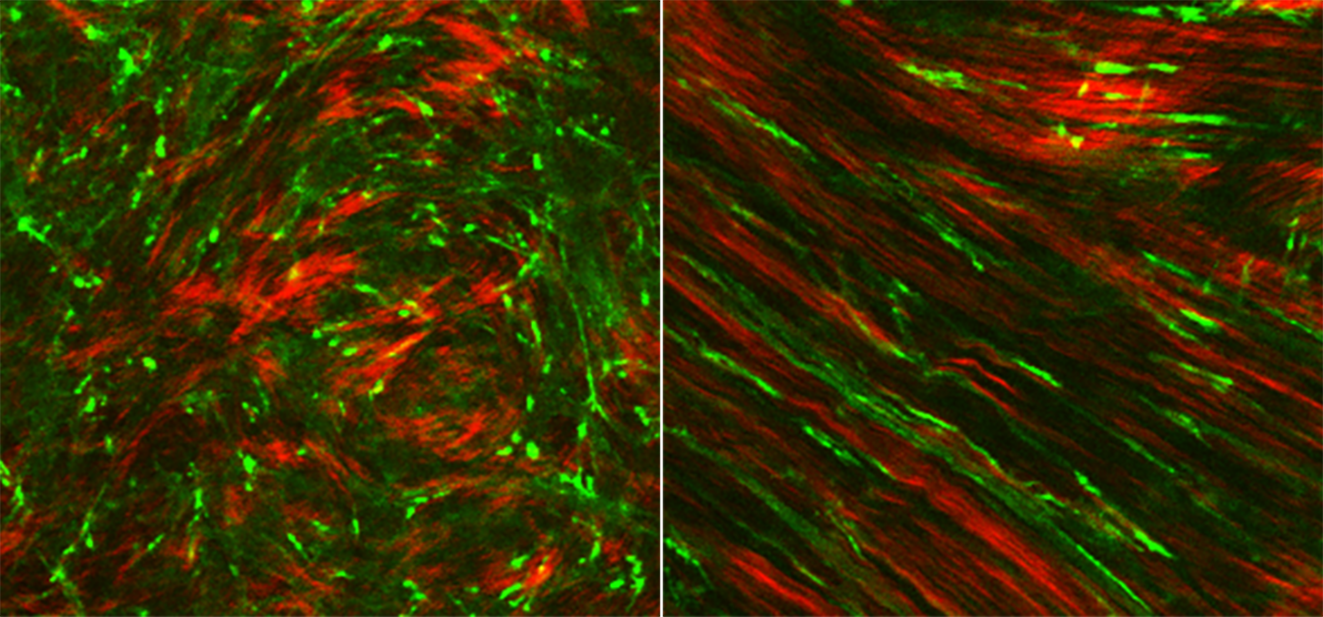

A 3-D model of ocular wound healing reveals how cells (green) compact and align extracellular collagen (red) through the generation of mechanical forces

Interactions between cells (green) and the extracellular matrix (red) following laser refractive surgery in the cornea provides insights into how healing and remodeling are regulated